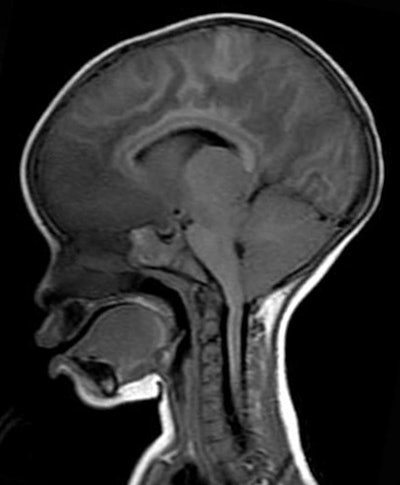

In the NEJM study, Taylor and colleagues assessed 348 children who were admitted to the hospital with cerebral malaria. Of those patients, 168 met the study criteria, including the presence of retinopathy. Twenty-five children (15%) died, and of this group, 21 (84%) had evidence of severe brain swelling on MRI when they were admitted to the hospital.

MR images revealed brain swelling in 39 (27%) of the 143 survivors, but that swelling eventually decreased after two to three days among the survivors. Taylor described that result as a "triumphant moment" in the study.

More importantly, the first piece of critical evidence came from one of the first patients scanned on the newly donated MRI. The child came to the hospital with typical cerebral malaria symptoms, including retinopathy. The comatose patient had an MRI on day 1 and a second one on day 2, but died four hours after the second scan.

While the MRI scan at autopsy revealed a swollen brain, there was no evidence of severe expansion. However, the MRI acquired during the first 24 hours after admittance showed clear evidence of the brain pushing down through a narrow hole, known as the foramen magnum, at the base of the skull.

"That area gets mushed and compressed if the brain is pushed out, and causes breathing to stop," Taylor said. "We would always look for that, but we never saw it. We could see it on the MRI and we instantly knew what happened. We never, ever would have seen it had we not captured it during life with the MRI."

Because of the pressure on the foramen magnum, the retinopathy-positive patients with cerebral malaria inevitably died because they stopped breathing.